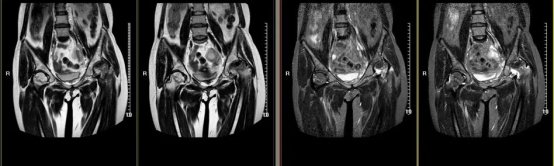

MR检查

对于早期股骨头缺血性坏死,MR是敏感的检查方法。当X线发现单侧股骨头缺血性坏死,一定要做MR检查,排除对侧是否受累。因为双侧发病多于单侧发病。

股骨头缺血性坏死MR表现